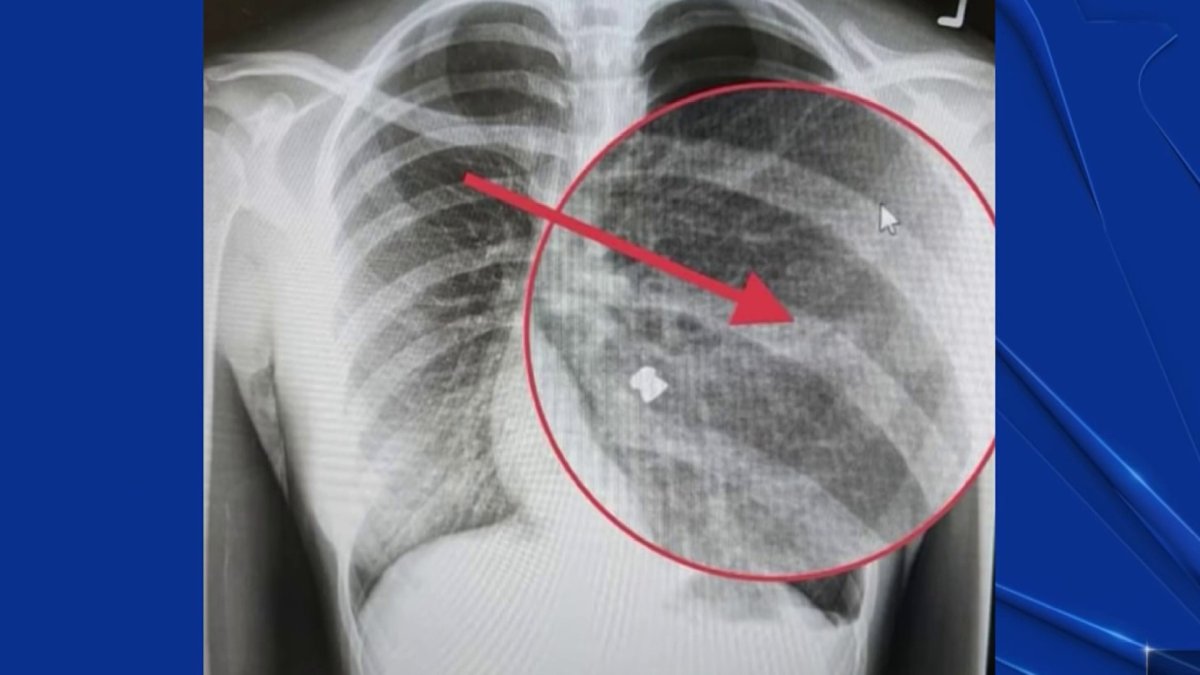

Bay Area teen's lung collapses after pellet gun attack Pellet Gun Shooter San Jose The incident caused internal bleeding and a collapsed lung, and sent the. Police arrested a man on tuesday suspected of a series of shootings from a pellet gun at seemingly random victims, which are. According to the san jose unified school district, a car drove by the campus in the. Police have arrested a man they suspect of using a. Pellet Gun Shooter San Jose.

'It almost killed me' San Jose teen suffers collapsed lung after Pellet Gun Shooter San Jose Police have arrested a man they suspect of using a pellet gun to shoot at least seven people, primarily girls and women, in san jose and campbell over the past six months. Police arrested a man on tuesday suspected of a series of shootings from a pellet gun at seemingly random victims, which are. The incident caused internal bleeding and. Pellet Gun Shooter San Jose.